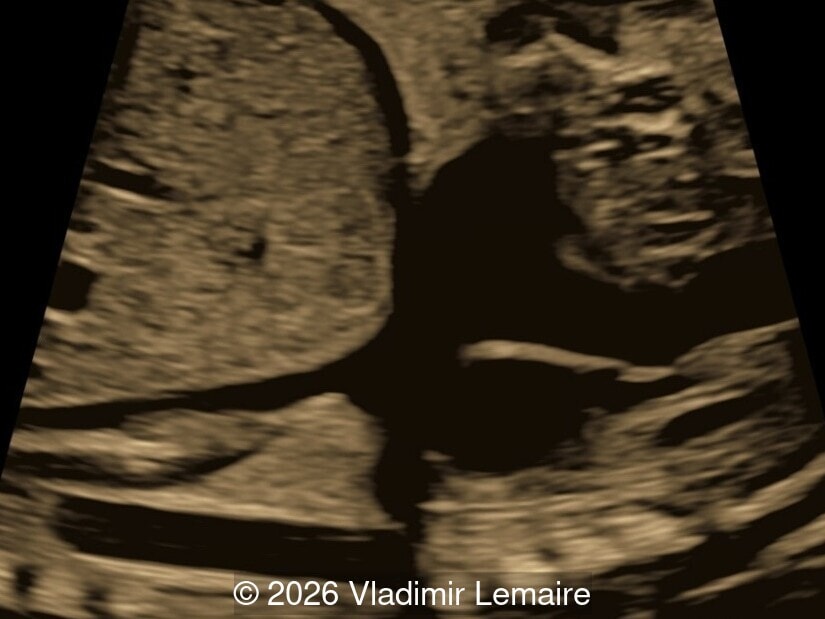

Transverse view of the upper abdomen at the level of the abdominal circumference.

Image 1 Transverse view of the upper abdomen at the level of the abdominal circumference.